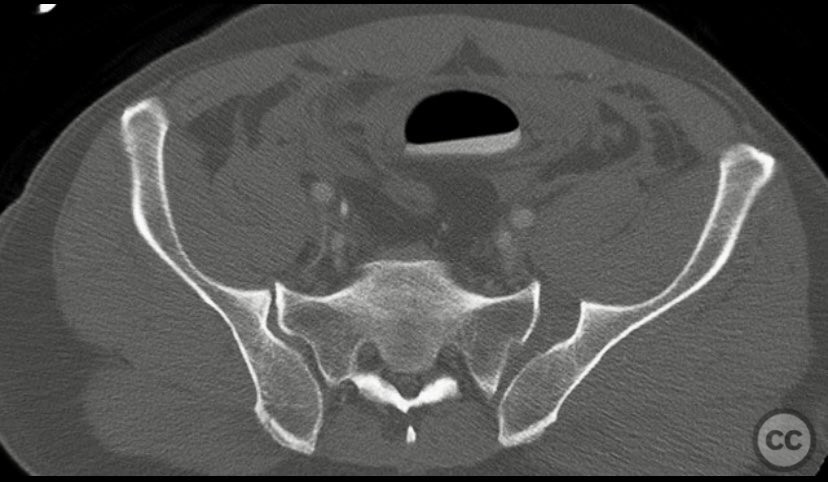

Pelvic Ring - AO/OTA 61x

Pelvis - AO/OTA 6x